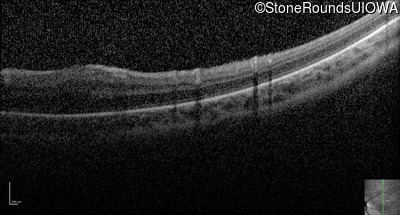

Optical Coherence Tomography - Left - 20/80

Exemplar / OCT Stack